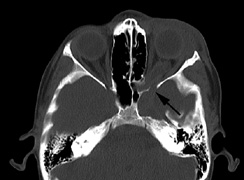

1. Schwannomas most commonly affect the fifth cranial nerve (CN), but any cranial nerve may be affected. In contrast to vestibular schwannomas (CN VIII), these typically do not grow large.84,90 Vestibular schwannomas (acoustic neuromas) are the classic finding in NF2 (Fig. 7). The risk for malignant transformation is low, but may be higher with radiation exposure.84,94

Fig. 7. Neurofibromatosis type 2: Images of a 12-year-old boy with deafness and weakness in his arms and legs, whose father has bilateral deafness. Axial T2-weighted (a) and postcontrast axial (b) T2-weighted images reveal bilateral vestibular schwannomas, which are also known as acoustic neuromas (arrows). This is the classic finding of NF2. (b, c) Bilateral schwannomas are seen in Meckel's cave (arrowheads) and a (d) lower left cranial nerve schwannoma extends into the pars nervosa of the jugular foramen (arrow). (e) A part cystic and part solid enhancing ependymoma in seen within the cervical cord and medulla and within the distal cord and conus. (e, f) Thoracic schwannomas are present at numerous levels (arrowheads). Marked enhancement and thickening of the roots within the cauda equina also represent multiple schwannomas.